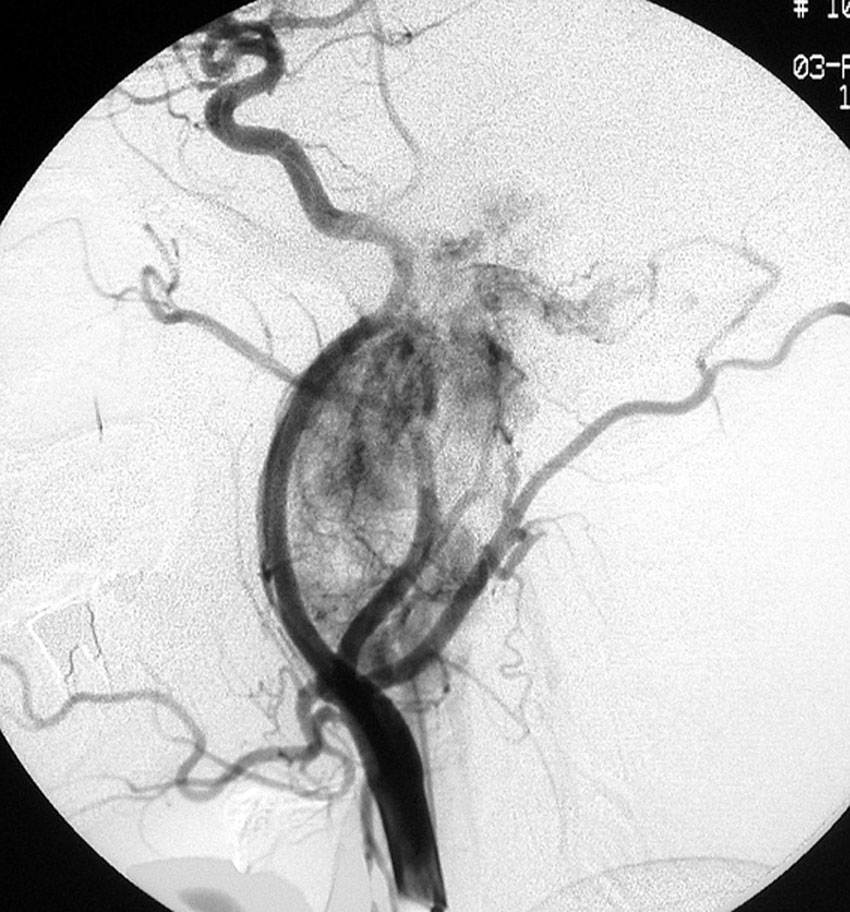

耳の聞こえと飲み込みが悪くなって発症(難聴と嚥下障害)した20代の患者さんのグロームス腫瘍 jugular paragangliomaです。左の頚動脈撮影 CAGでは,頸部の腫瘍におされて内頚動脈が前方に屈曲しています。外頚動脈から多くの血管が流入して血管腫のように濃い腫瘍陰影がみえます。右側の椎骨動脈撮影 VAGでは,頚静脈孔から頭蓋内の小脳延髄角部まで伸びた腫瘍が染まります。頭蓋内はPICAから頸静脈球と頸部には椎骨動脈の筋肉枝からの腫瘍血管がみられます。

頸部から頸静脈球を抜けてS上静脈洞内に入ります。これはクラスCかDか迷うところです。ちょっと難しい。またこのサイズでは,迷走神経と舌咽神経の機能を温存することができません。延髄方向へ伸展していますし年齢が若いので手術せざるを得ないものでした。

この腫瘍は放射線治療で制御できるものではないでしょう。手術で全摘出できて10年以上再発はありません。嚥下障害と強い嗄声が残りましたが,働いて社会生活はできています。